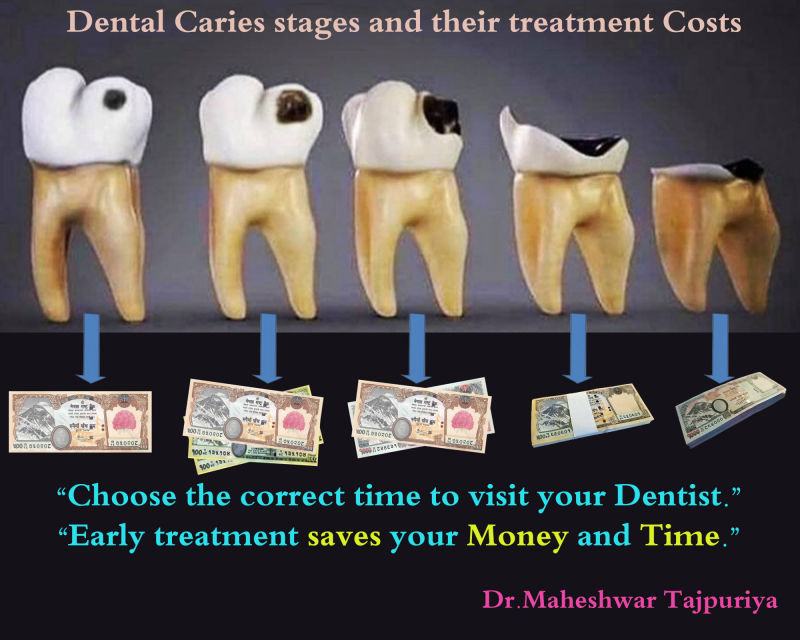

Bite Injury Dental Treatment & Cost

Dental Treatment & Cost Dental Stomattis